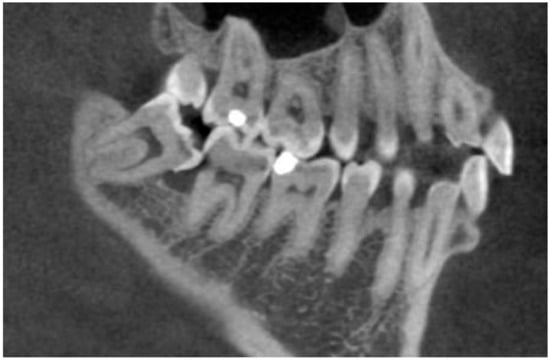

The presence of ERR was evaluated by navigating the volume of CBCT and exploring all sections of the second molar in all dimensions and was recognized as an apparent loss of substance on the distal surface of the adjacent second molar root. Suspicion of resorption was registered if a contact was seen between the third and second molars in addition to a change in the shape of the surface of the second molar (Figure 2). External root resorption of adjacent second molars was differentiated from carious lesions based on their radiographic appearance: in all cases where the change in the shape of the surface of the second molar was observed, but there was a clear gap between second molars and the dental crown of the third molar, this lesion was diagnosed as caries, and the tooth was recorded as free of ERR.

Figure 2.

External root resorption of the lower second molar.